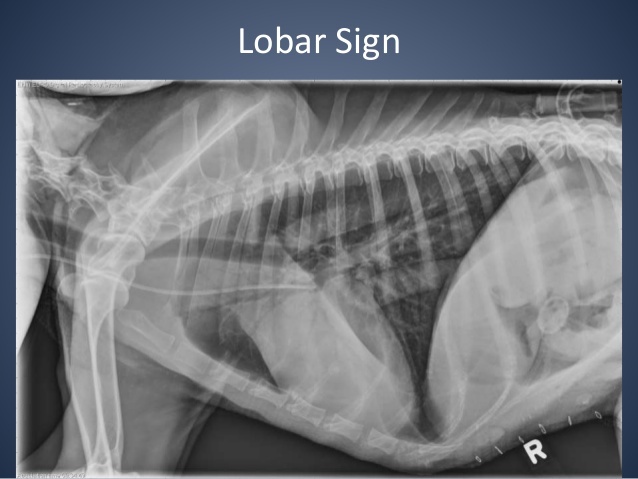

“Lobar Sign”